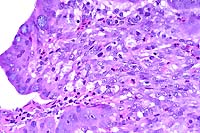

- Case 16-1. Lung. Central area of cavitary necrosis

is surrounded by congested, consolidated lung parenchyma.

- Case 16-1. Lung. Numerous acid fast bacilli are scattered

throughout caseous necrotic debris.

- AFIP Diagnosis: Lung: Pneumonia, granulomatous and

necrotizing, diffuse, severe, with cavitation and mineralization,

Matschie's tree kangaroo (Dendrolagus matschiei), marsupial.

- In the group of diseased tree kangaroos studied by the contributor,

gross and microscopic lesions due to MAC infection have been

observed in several organ systems. However, the most extensive

lesions have occurred in the lungs and bones, and were histologically

characterized by necrotizing pyogranulomatous pneumonia and osteomyelitis

with numerous acid-fast bacilli. The Ziehl-Neelsen and Fite's

staining methods performed at the AFIP demonstrated acid-fast

bacilli in a section of lung from this tree kangaroo.